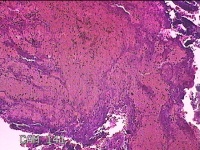

性别

女

年龄

35岁

临床诊断

异常子宫出血:①子宫内膜息肉 ②子宫内膜憩室 ④子宫内膜炎

一般病史

阴道不规则流血9个月。

标本名称

宫腔内组织

大体所见

灰白暗红色不规则碎组织2.3x2x0.8cm一堆。